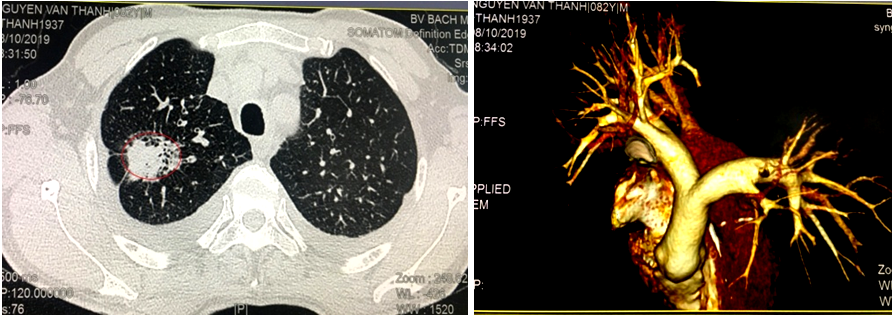

10. Xạ hình xương

Hình ảnh tổn thương xương đa ổ dọc theo các đốt sống, xương chậu và xương sườn hai bên nghĩ tới tổn thương thứ phát.

Hình 2. Hình ảnh xạ hình xương